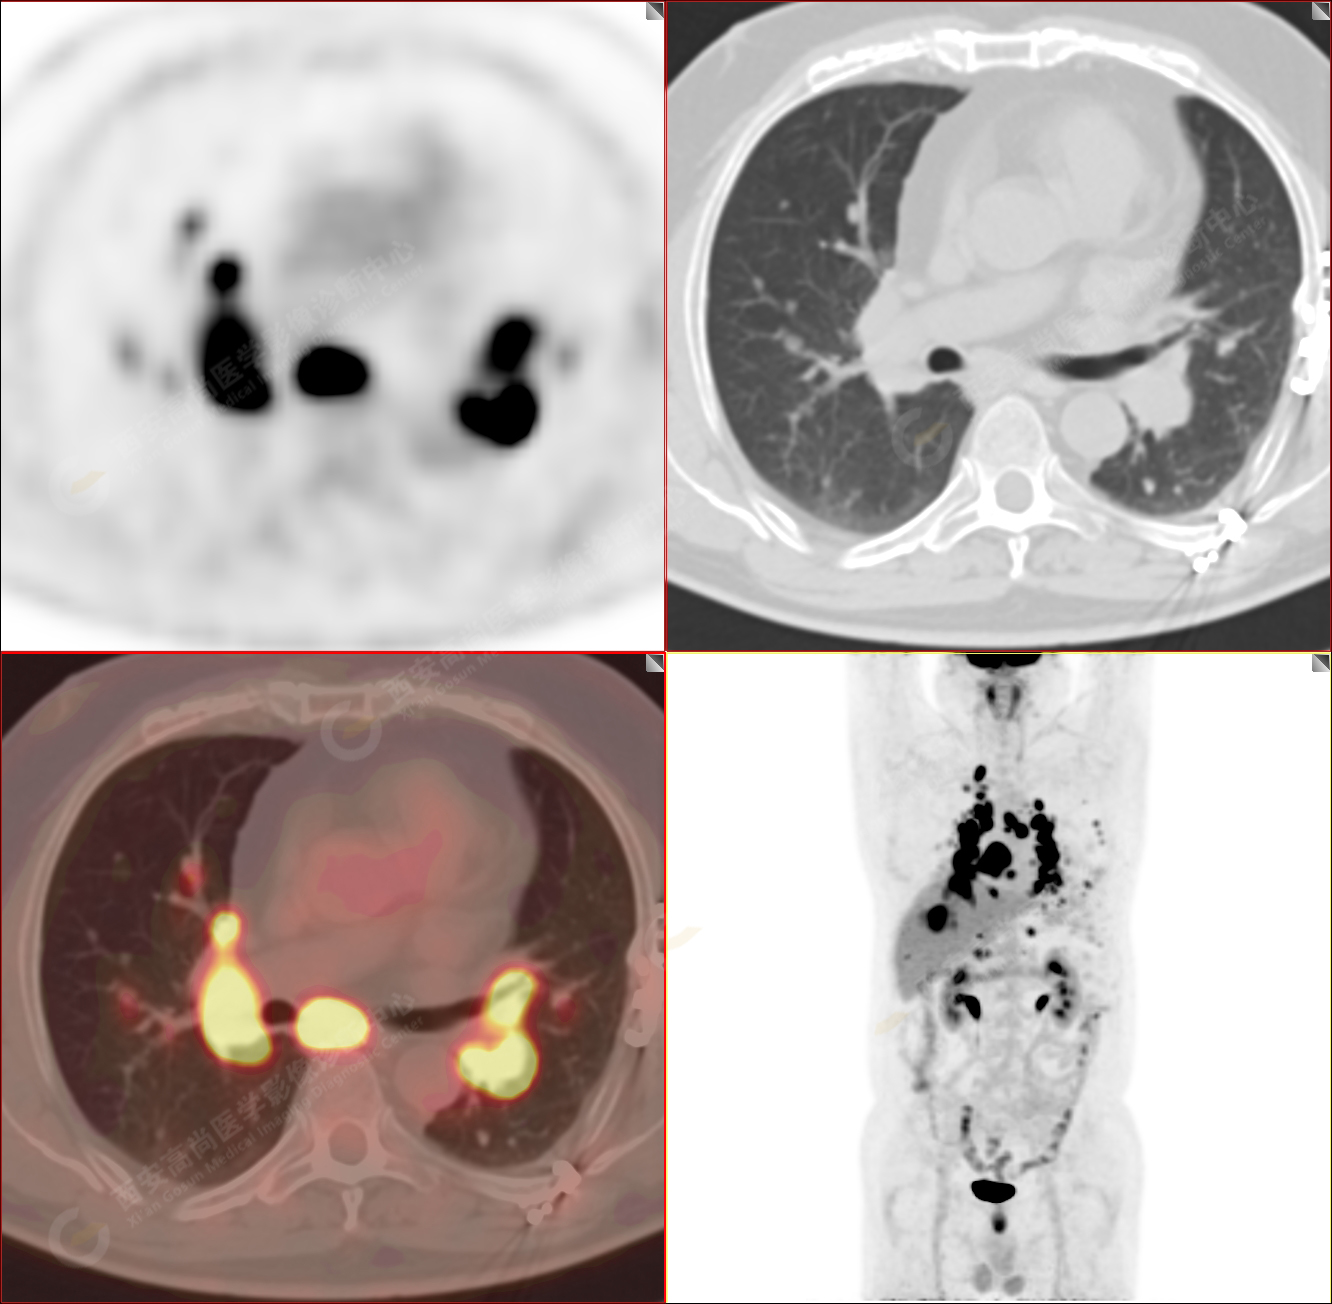

男性,53歲,頭暈半月入院,CT發(fā)現(xiàn)肺內(nèi)腫塊,雙肺多發(fā)大小不等實(shí)性及粟粒樣結(jié)節(jié),雙肺門(mén)及縱隔多發(fā)腫大淋巴結(jié)。病程中無(wú)發(fā)熱、胸悶氣及胸部不適。既往:左側(cè)肋骨外傷史。

PET/CT圖像